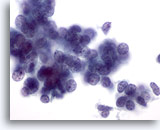

画像 2

肺FNA、肺大細胞癌明瞭な細胞縁を呈するシート状低分化癌細胞。細胞は統制されておらず、局所的に核の重積が見られます。背景には何も見られず、腫瘍性背景を呈していません。腫瘍細胞には、扁平上皮ないし腺管への分化に特異的な特徴は認められません。

40倍

画像 2

肺FNA、肺大細胞癌

明瞭な細胞縁を呈するシート状低分化癌細胞。細胞は統制されておらず、局所的に核の重積が見られます。背景には何も見られず、腫瘍性背景を呈していません。腫瘍細胞には、扁平上皮ないし腺管への分化に特異的な特徴は認められません。

40倍